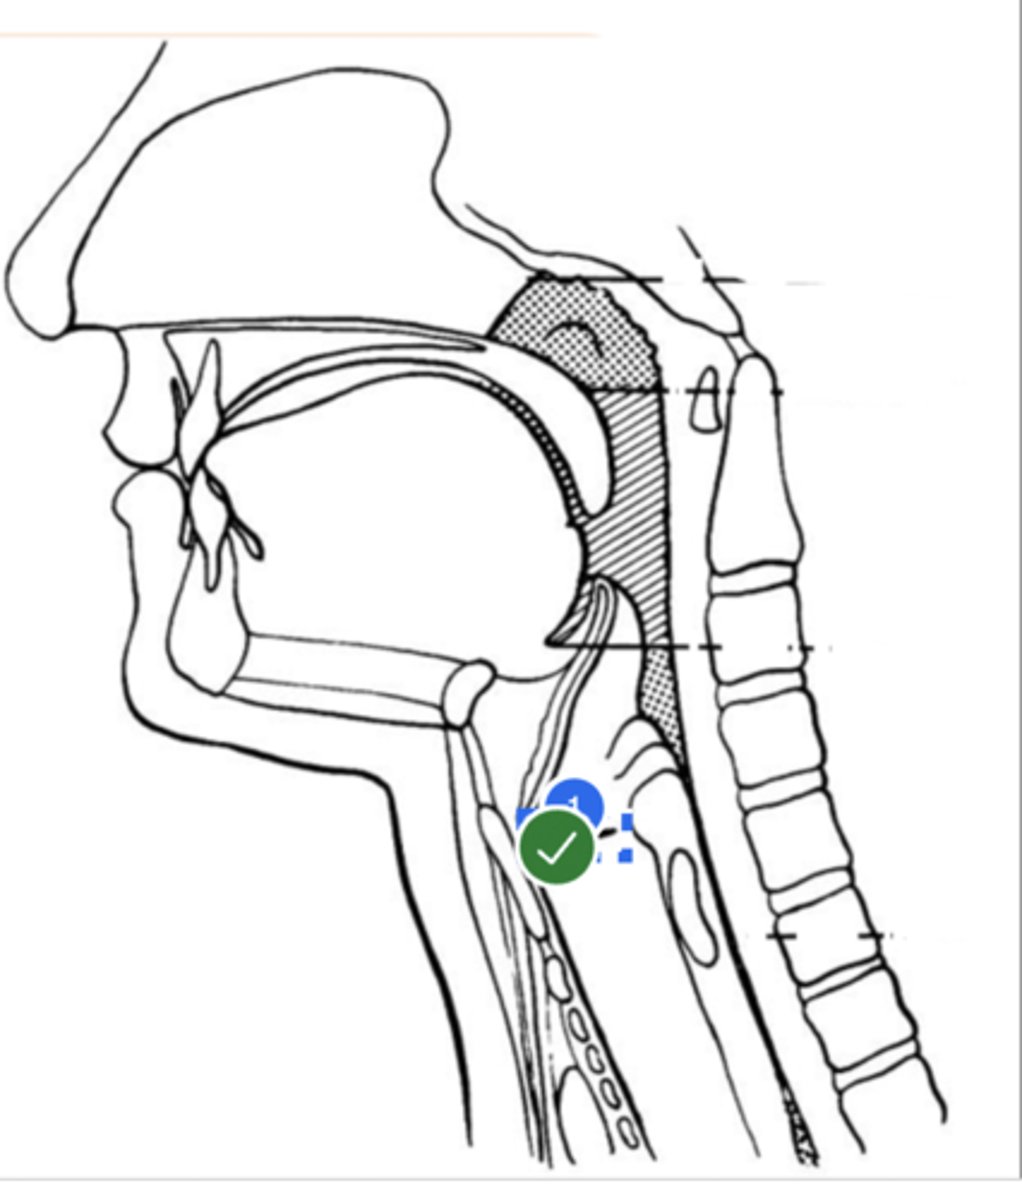

Label Nasopharynx (lateral view)

Label Nasal cavity (lateral view)

Label oropharynx (lateral view)

Label hypopharynx/ hylolarynx

Label tongue (lateral view)

Label soft velum/ palate (lateral view)

Label hard palate (lateral view)

Label mandible (lateral view)

Label base of tongue (lateral view)

label hyoid bone (lateral view)

Label epiglottis (lateral view)

label Line of true vocal folds (lateral view)

label Thyroid cartilage (anteriorly) (lateral view)

Label posterior cricoid (lateral view)

Label esophagus (lateral view)